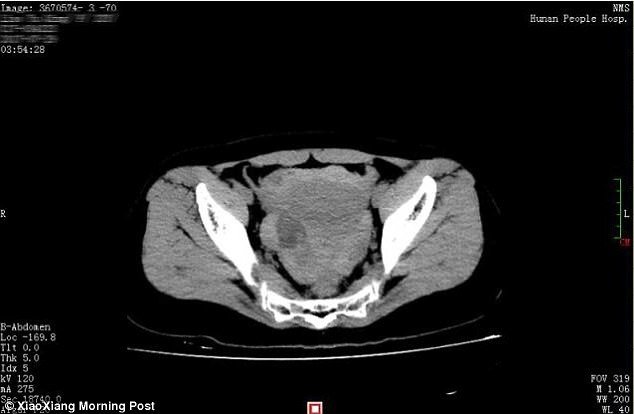

Cô vợ suýt chết vì sex quá đà làm vỡ nang buồng trứng

Xa nhau lâu ngày, vợ chồng Xiao Qing (Trung Quốc) "yêu" quá nồng nhiệt tới mức nang buồng trứng bị vỡ gây xuất huyết nghiêm...